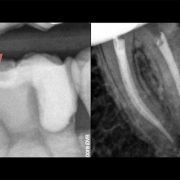

Based on evidence, all posterior teeth should be restored with cuspal coverage after root canal treatment. However, most of these teeth are badly destructed due to caries or large existent restoration. The key of success is to preserve the remaining tooth structure and restore the tooth conservatively. Dr khalid Merdad and I worked simultaneously to accomplish this task.